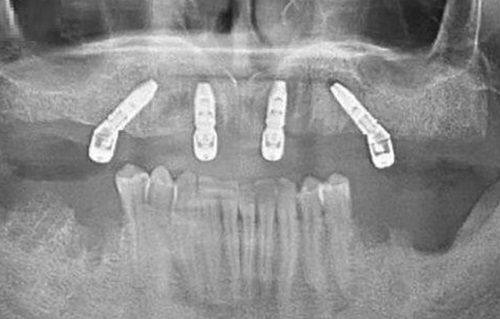

其中,龈下刮治是临床推荐的专精医疗清除方法,专门解决常规洗牙无法处理的龈下牙结石问题。常规洗牙仅能清除牙冠表面的牙结石,若牙结石蔓延至牙龈下方,会持续刺激牙周组织,引发牙龈出血、牙周炎,甚至导致牙齿松动。此时就需要通过龈下刮治处理:医生会将专用的精细工具深入牙龈乳头下,精细刮除牙根和牙周袋内的牙结石、菌斑,过程中可能会根据情况进行局部麻醉,减轻患者不适感。尤其当确诊为牙周炎时,洗牙后必须配合龈下刮治,才能完全清除病灶,防止牙周问题进一步恶化。

龈下刮治是经过临床验证的专精手段,医生能通过专用工具精细清除牙根和牙周袋内的牙结石、菌斑,从根源上解决牙周炎症的诱因。对于已经确诊牙周炎的患者,龈下刮治更是必不可少的治疗环节,只有配合洗牙完成龈下刮治,才能阻止牙周组织的进一步破坏,避免牙齿松动、脱落等重度后果。相比之下,民间方法仅能作为轻度牙结石的辅助清洁手段,不能替代专精医疗干预。

若想更快清除牙结石,同样优先选择专精医疗手段。龈下刮治一般根据牙结石的重度程度,分1-4次完成,每次处理特定区域的牙齿,能在较短时间内完全清除顽固的龈下牙结石,解决因牙结石引发的口腔问题。